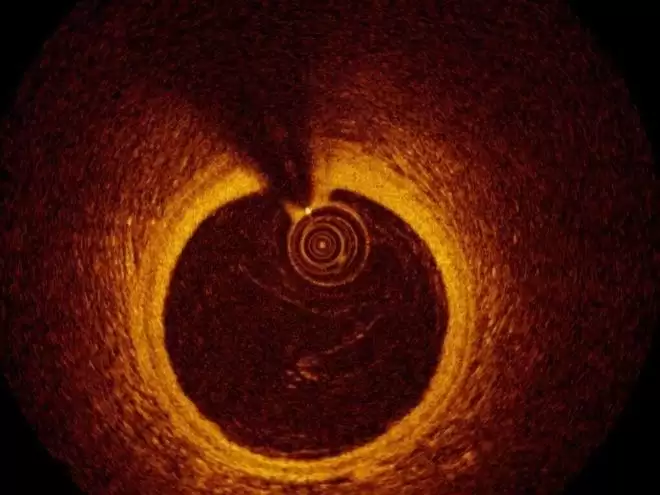

据《2024 年全球心血管疾病负担报告》统计,每年因心血管疾病死亡的人数达 1920 万,而经皮冠状动脉介入治疗(PCI)作为最核心的血运重建手术,全球年手术量已超过 400 万例。在 PCI 手术中,OCT(光学相干断层成像)被称为医生的「第三只眼」,可清晰看到血管内病变情况,但是其图像解读高度依赖医生经验,初级医师与资深专家在手术成功率、并发症发生率等关键指标上的差距高达 40% 以上。

腔内影像中不同技术与分辨率的对比示意图